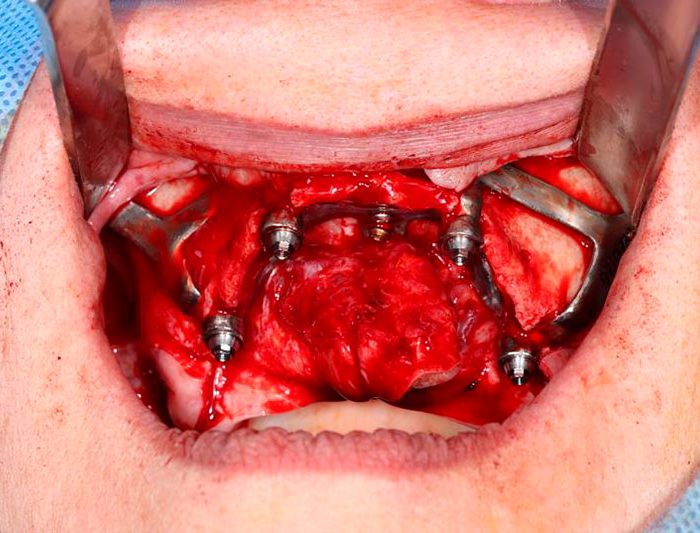

Design My Implants uses CT scans to create tailored bone reconstruction systems. Our titanium parts are finely polished and treated for optimal bone bonding. We strategically place the device and screws for maximum durability. The screws are set in the densest bone areas for secure fixation. Our entire process emphasizes precision for lasting results.

- Immediate Reconstruction Without Bone Grafting

Our subperiosteal implants are designed to adapt to any bone structure, making them suitable for a wide range of patients, regardless of their bone density or volume.